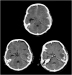

Evidenzbasierte Neurotraumatologie Journal für Neurologie, Neurochirurgie und Psychiatrie 2008; 9 (3): 20-27 Volltext (PDF) Summary Praxisrelevanz Abbildungen Keywords: Neurochirurgie, Neurotraumatologie Evidenzbasierte Medizin bedeutet die individuelle klinische Erfahrung mit der besten verfügbaren Evidenz aus systematischer Forschung zu vereinbaren. In der Neurotraumatologie lassen sich in der Akutphase kaum prospektive randomisierte Studien durchführen. Während der Behandlung von Patienten mit Schädelhirntrauma (SHT) kommt es immer wieder zu alltäglichen Fragestellungen, wie Zeitpunkt des Beginns der Thromboseprophylaxe, antikonvulsive Prophylaxe, Indikation und Art der Hirndruckmessung, Häufigkeit zerebraler CT-Kontrollen, auf die wir uns wissenschaftlich fundierte Antworten wünschen. Ziel dieser Arbeit war es, evidenzbasierte Antworten auf diese Fragen zu finden. Die zu den einzelnen Fragestellungen publizierten Studien wurden in prospektiv-randomisierte, retrospektive Studien und Fallberichte unterteilt. Dementsprechend ließ sich eine Therapierichtlinie bezogen auf spezifische Fragestellungen herausarbeiten. Bei fehlender wissenschaftlicher Grundlage wurden Therapieempfehlungen ausgearbeitet und in einigen Fällen ließ sich nur auf Expertenmeinungen hinweisen. |